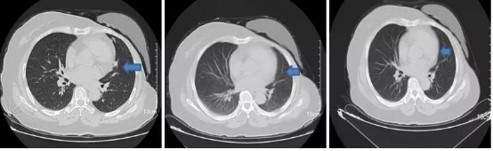

图4:患者肺部转移灶(从左至右依次为:治疗基线、治疗后3个月)

图6:患者肺部转移灶(从左至右依次为:治疗基线、治疗后3个月、6个月)